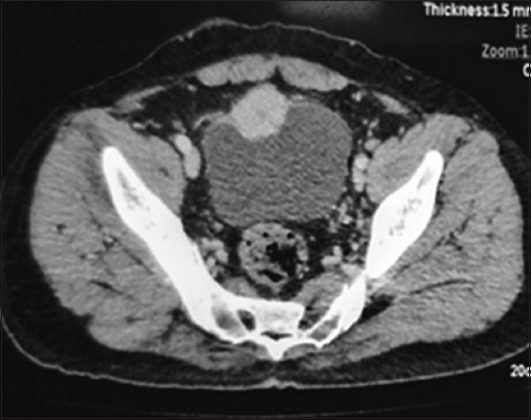

Case presentation: Presented here are three cases of incidental urinary bladder paraganglioma, all having hematuria as the primary symptom. During transurethral resection of bladder tumor, blood pressure fluctuated intensely with profuse bleeding, leading to the abandonment of the procedure. The patients were later diagnosed as having paraganglioma, and then, they were subjected to systemic evaluation and definitive treatment.